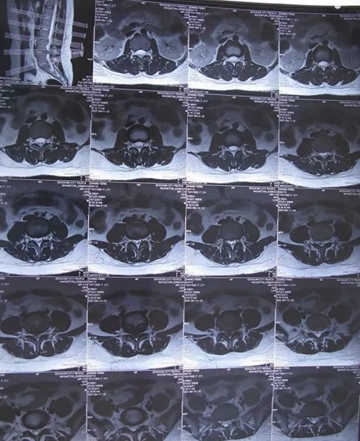

核磁矢状位

核磁轴位

2011年,小张(20岁),L4-5椎间盘脱出,高密人民医院、青岛山大医院要求手术。右腿外侧疼痛,迈不开步子,直腿抬高不过20°。